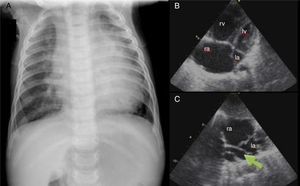

Case report 3 (total anomalous pulmonary venous connection)A six-month-old male infant was referred to our hospital for respiratory distress and failure to thrive. Physical examination showed transcutaneous oxygen saturation 90%, respiratory rate 50 cpm, and subcostal and inferior intercostal retractions. Symmetrical and wide peripheral pulses were observed, a faint systolic murmur was audible over the left sternal border, and the liver was palpable 2 cm below the right costal margin. The chest X-ray (Figure 3A) showed cardiomegaly and moderate pulmonary venous congestion. Echocardiography (Figure 3B and C) showed a dilated right atrium and ventricle, a small left atrium and a small ostium secundum type atrial septal defect (ASD). No pulmonary venous connection to the left atrium could be identified, and there was evidence of an abnormal pulmonary venous confluence behind the left atrium. A diagnosis of TAPVC was made. The patient underwent surgery in order to redirect pulmonary vein flow to the left atrium and to close the ASD. Since then, his growth and development have been appropriate for his age.

(A) Chest X-ray showing cardiomegaly and moderate pulmonary venous congestion; (B) dilatation of the right chambers; (C) total anomalous pulmonary venous connection, with no communication between the pulmonary veins and left atrium and a common vertical vein (arrow). la: left atrium; lv: left ventricle; ra: right atrium; rv: right ventricle.